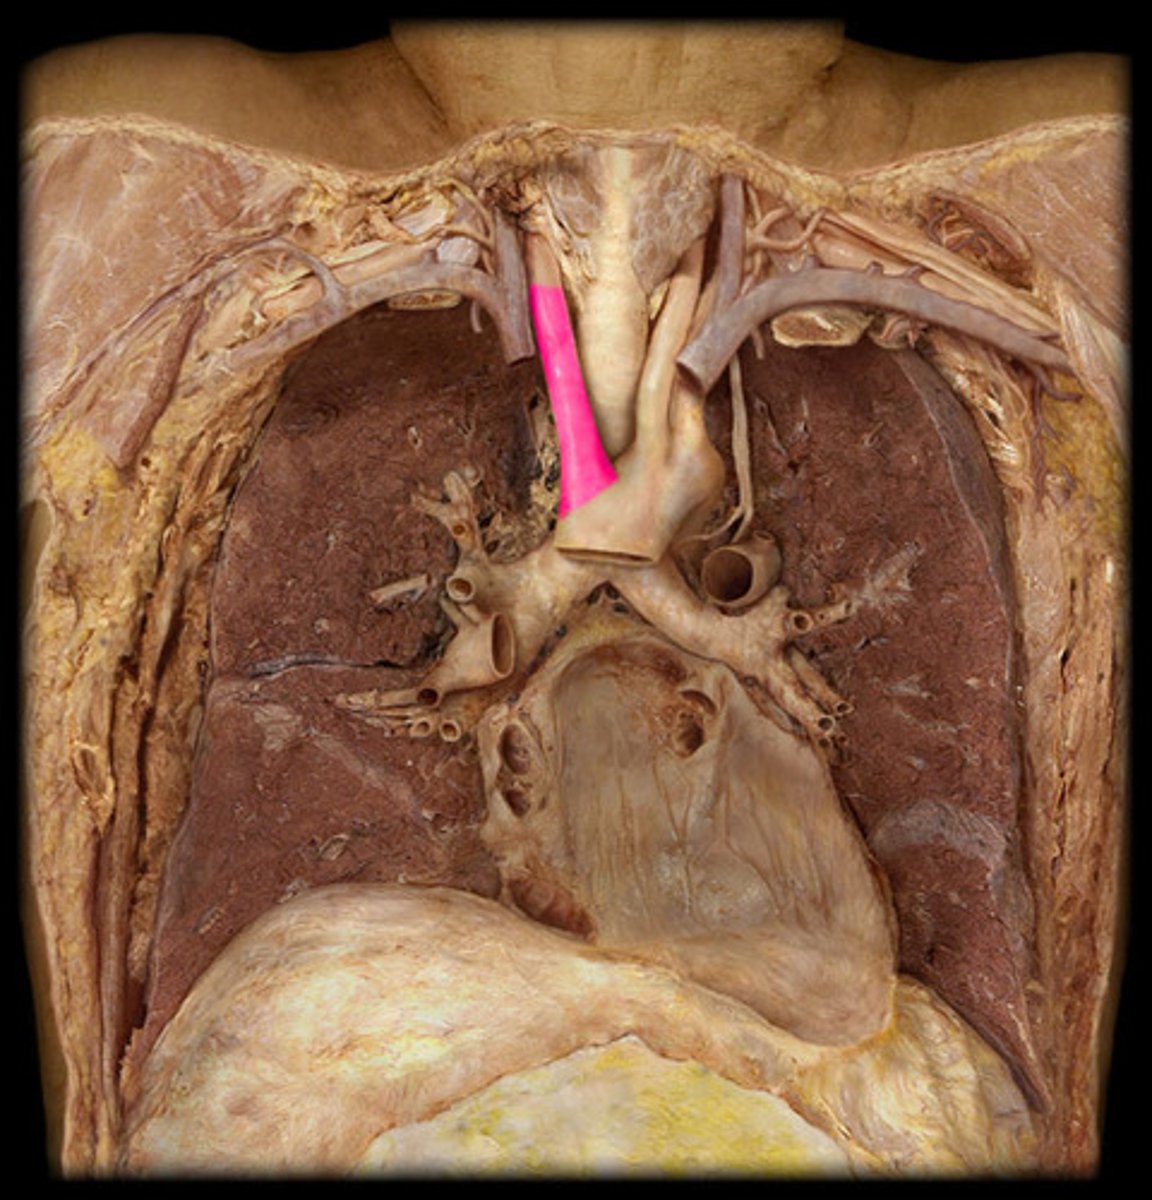

ligamentum arteriosum

webbing connecting aorta and pulmonary trunk

12

BQ: vestige of the fetal ductus arteriosus, which shunted blood in the pulmonary trunk away from the lungs in the fetus